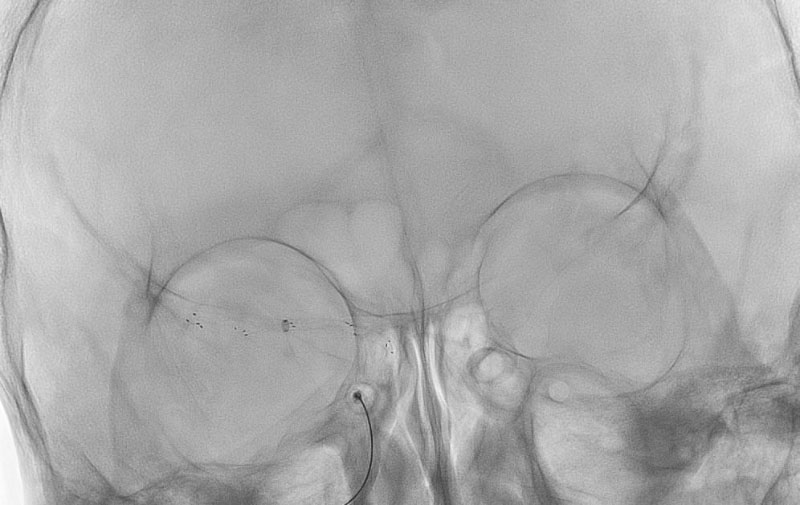

No.1596 手術前